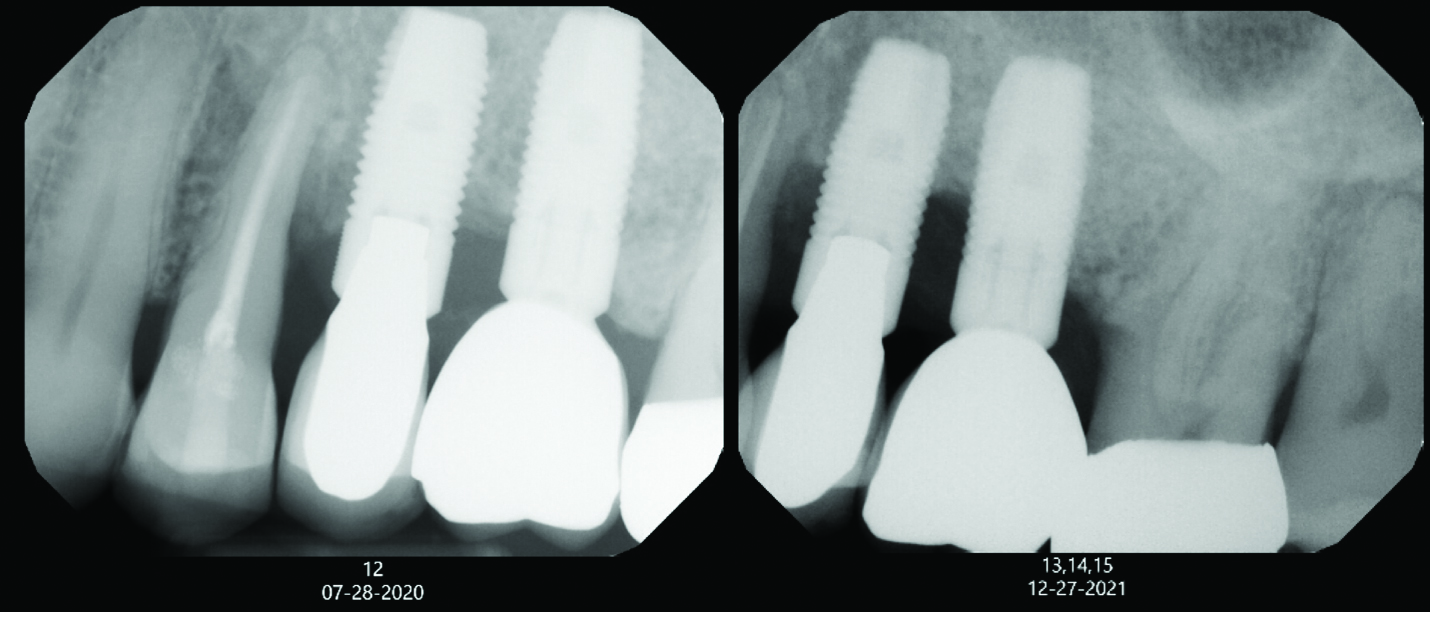

A degree of personalization is involved in implant maintenance therapy beginning with an evaluation of the patient's motivation and ability to maintain good oral hygiene prior to implant placement.27 Patient compliance is essential, and inadequate oral hygiene may be a contraindication to implant placement.10 Research shows that plaque buildup surrounding implants might exacerbate mucositis lesions after only 3 months of plaque accumulation.28 Therefore, similar to periodontal maintenance, peri-implant maintenance should be performed every 3 months.9,28 Clinical parameters for monitoring dental implants include probing depth, presence of bleeding on probing (BOP), suppuration, mucosal redness, plaque, keratinized mucosa, occlusion/prosthetic stability, and vestibular depth.10,11 Maintenance visits should also include radiographic evaluation if necessary, a review of the patient's medical history, and demonstration/evaluation of the patient's oral hygiene habits.9,10 Any changes in medical history, such as the onset of diabetes, and/or ability to maintain oral hygiene may affect the patient's susceptibility to peri-implantitis (Figure 1).

Fig 1. A patient radiograph from July 2020 is seen on the left. Just 1.5 years later, in December 2021, the patient presented with significant bone loss at implant sites Nos. 13 and 14, as seen on the right. The patient had become an uncontrolled diabetic during this time. This case emphasizes how changes in medical history, such as developing diabetes, can affect the peri-implant supporting structures.

Figure 1